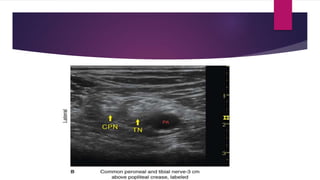

POPLITEAL SCIATIC NERVE BLOCK

• Division sciatic nerve usually occurs between 4-10 cm proximal to popliteal fossa

crease.

• In popliteal fossa Tibial nerve is lateral & superficial to popliteal artery and vein, and